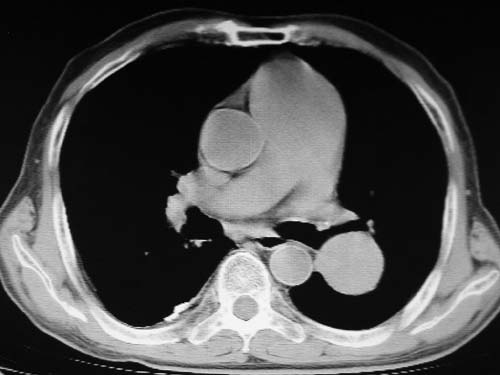

男,80岁

左肺动脉异常增粗,建议增强。

肺动脉瘤。建议先行ct增强扫描

左肺动脉异常增粗,考虑肺动脉狭窄可能。

1)考虑左肺动脉瘤可能性大,建议增强。2)右肺上叶继发性肺结核。3)右侧胸膜增厚、钙化,左侧胸膜反应。

肺动脉段突出,左右肺门不等大,左肺门明显增大,肺动脉干及左肺动脉明显增宽,考虑先天性肺动脉狭窄瓣膜狭窄型。

)考虑肺动脉扩张,右心室增大,主动脉弓段正常位弓后段明显变小(不会是动脉导客未闭吧,不知患者有何症状病史)0。2)右肺上叶继发性肺结核。3)右侧胸膜增厚、钙化,左侧胸膜反应。

右肺上叶尖段结核;左肺下叶占位?建议增强扫描。右侧胸膜增厚;右肺局限性肺气肿。

结合患者年龄,不除外左下肺扩张性动脉瘤,建议胸透是否有扩张性博动,以便确诊。

肺动脉高压,左肺动脉瘤样扩张。